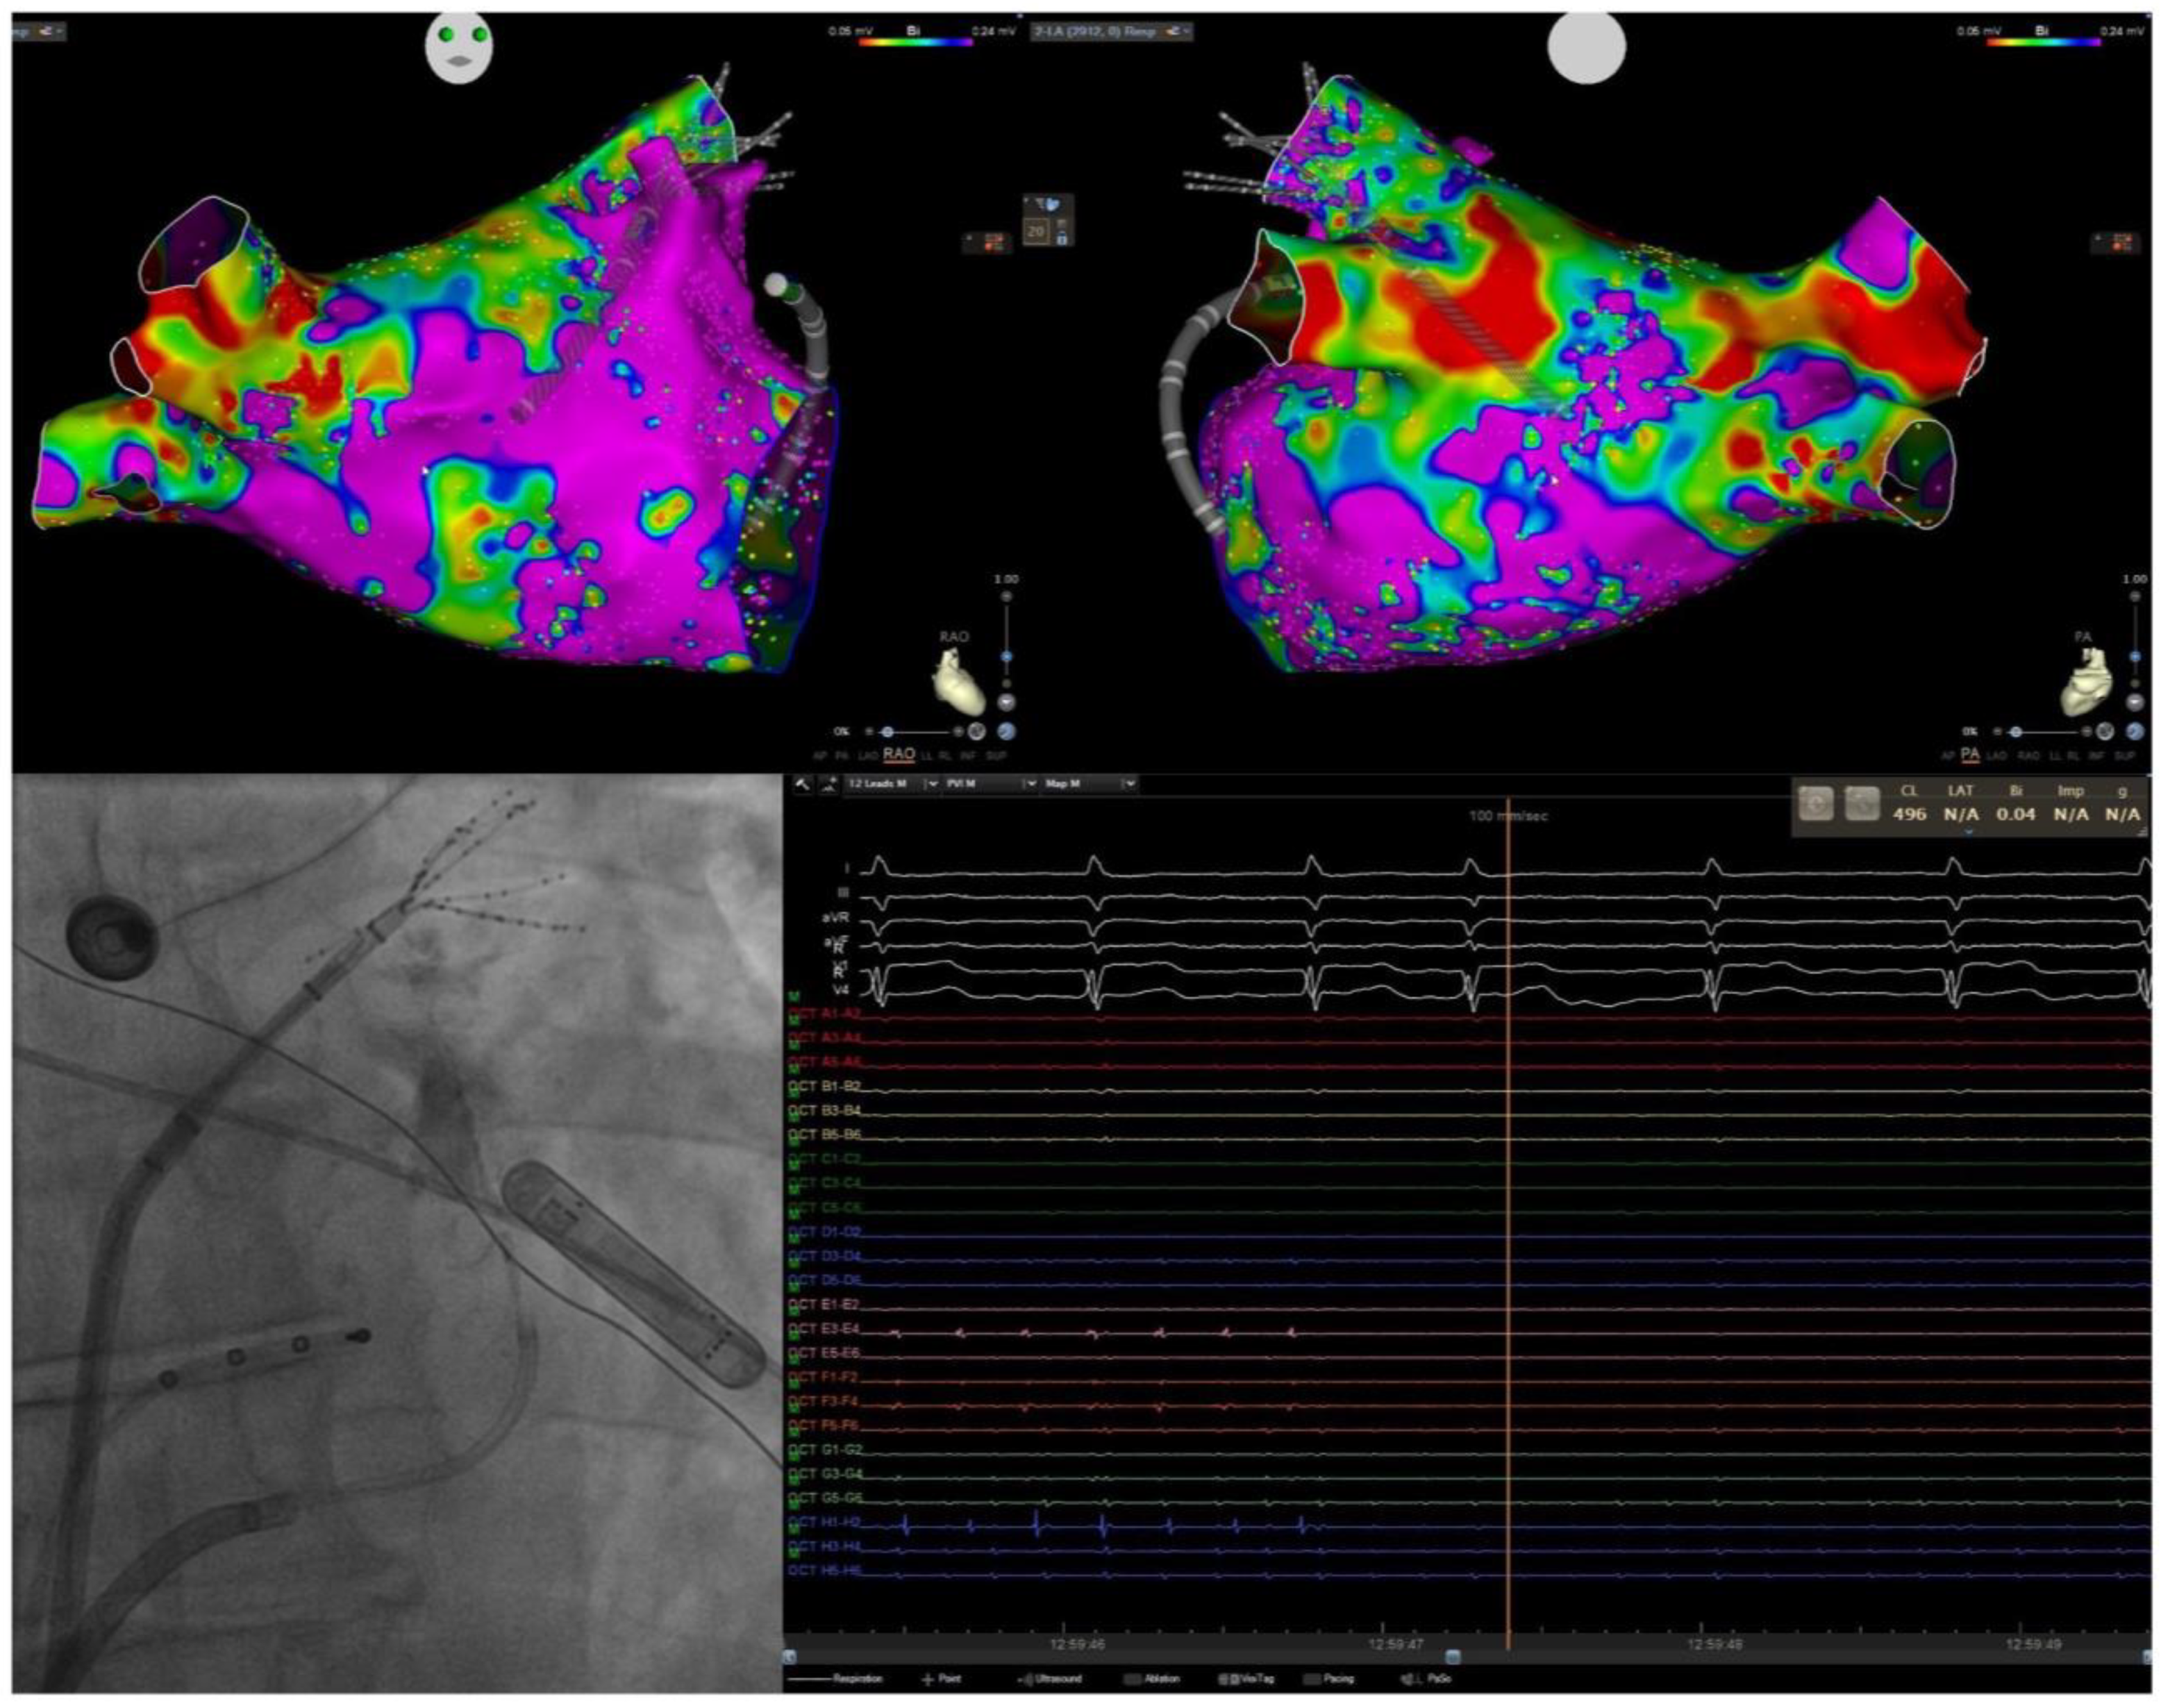

- Rolf, S.; Kircher, S.; Arya, A.; Eitel, C.; Sommer, P.; Richter, S.; Gaspar, T.; Bollmann, A.; Altmann, D.; Piedra, C.; et al. Tailored Atrial Substrate Modification Based on Low-Voltage Areas in Catheter Ablation of Atrial Fibrillation. Circ. Arrhythmia Electrophysiol. 2014, 7, 825–833. [Google Scholar] [CrossRef] [PubMed]

- Li, K.; Xu, C.; Zhu, X.; Wang, X.; Ye, P.; Jiang, W.; Wu, S.; Xu, K.; Li, X.; Wang, Y.; et al. Multi-Centre, Prospective Randomized Comparison of Three Different Substrate Ablation Strategies for Persistent Atrial Fibrillation. Europace 2023, 25, euad090. [Google Scholar] [CrossRef]